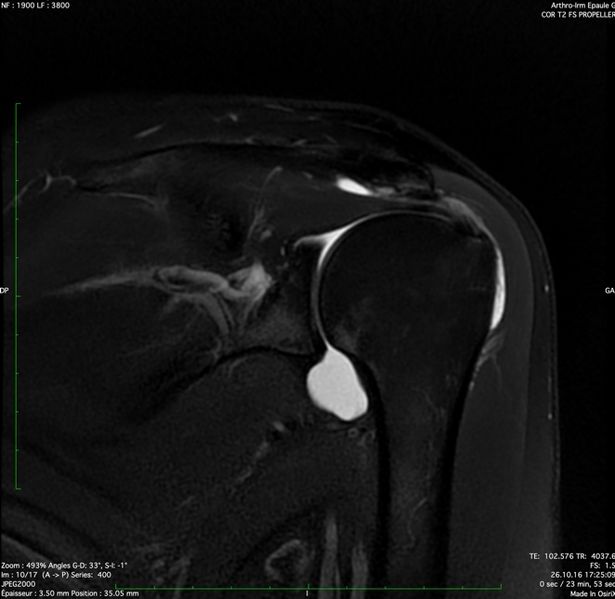

Magnetic resonance arthrography (MRA) of a left subacromial impingement. Note the important compression done by the acromion and the coracoacromial ligament on the supraspinatus tendon.